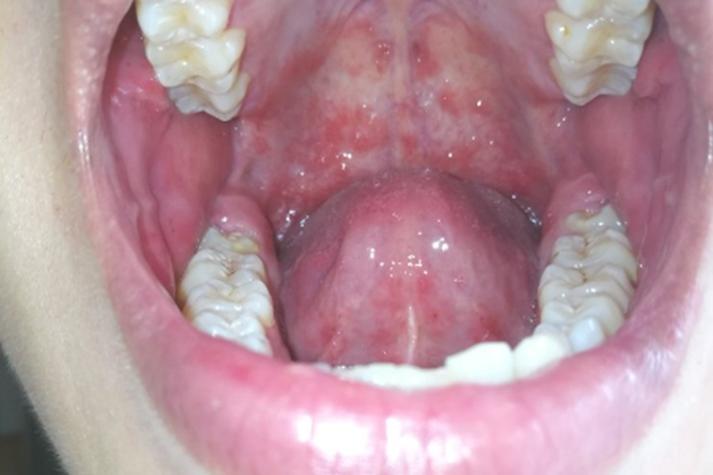

儿童口腔上颚红斑是何原因?

儿童口腔上颚(硬腭)出现红斑,可能由多种原因引起,从轻微的生理现象到需要治疗的感染都有可能,以下是几种最常见的情况,并附上文字描述和特征,帮助您进行初步判断。

- 周围黏膜: 红斑(或白色斑片)周围的黏膜通常会有明显的发红、充血。

- 外观: 早期口腔上颚、舌头、颊黏膜、牙龈等处出现散在的、针尖大小的红色斑丘疹或水疱。

- 发展: 水疱很快会破溃,形成灰白色的小溃疡或糜烂面,周围有一圈红色的晕。

- 外观: 口腔黏膜(包括上颚)出现大面积的、边界不清的鲜红色或紫红色斑片。